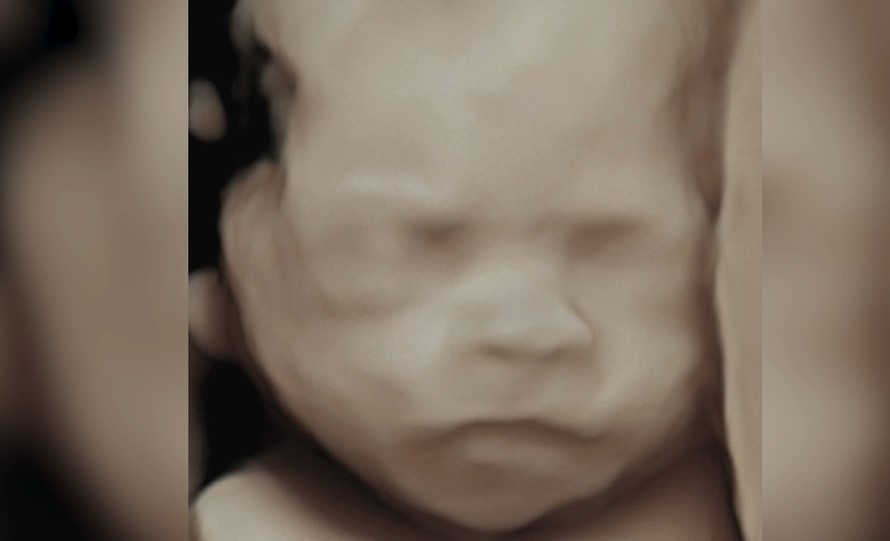

¡Momento muy especial! Mayeli Díaz, ex de La isla de las tentaciones, ha revelado en exclusiva en su canal de mtmad la cara de su hija Alma gracias a una ecografía 5D superavanzada en 8K. La imagen es hiperrealista y se ve con todo lujo de detalles: naricita, boquita, ojitos… ¡parece una foto de recién nacida!

Aquí las fotos que ha compartido ella de la ecografía con efecto realista y la foto normal:

Las fotos